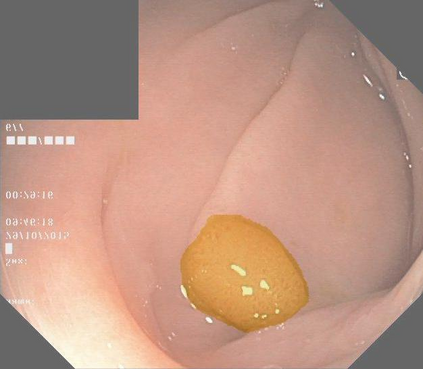

Image segmentation is a fundamental task in image analysis and clinical practice. The current state-of-the-art techniques are based on U-shape type encoder-decoder networks with skip connections, called U-Net. Despite the powerful performance reported by existing U-Net type networks, they suffer from several major limitations. Issues include the hard coding of the receptive field size, compromising the performance and computational cost, as well as the fact that they do not account for inherent noise in the data. They have problems associated with discrete layers, and do not offer any theoretical underpinning. In this work we introduce continuous U-Net, a novel family of networks for image segmentation. Firstly, continuous U-Net is a continuous deep neural network that introduces new dynamic blocks modelled by second order ordinary differential equations. Secondly, we provide theoretical guarantees for our network demonstrating faster convergence, higher robustness and less sensitivity to noise. Thirdly, we derive qualitative measures to tailor-made segmentation tasks. We demonstrate, through extensive numerical and visual results, that our model outperforms existing U-Net blocks for several medical image segmentation benchmarking datasets.